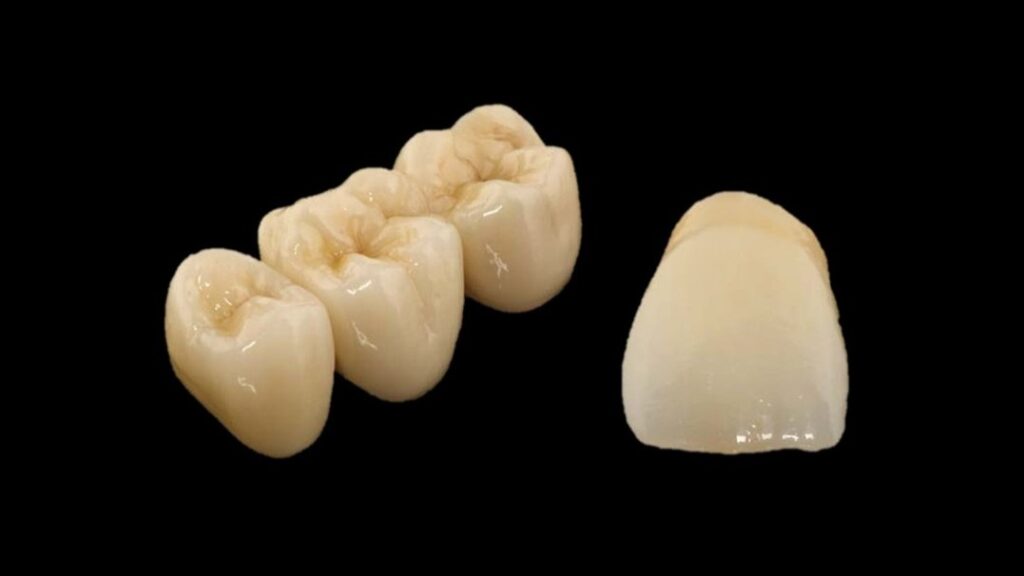

Crown & Bridge

All-ceramic crown and bridge restoration is a common restorative method that uses high-strength, pure ceramic materials that closely resemble the color of natural teeth to make crowns or bridges, and is used to repair damaged, discolored, or missing teeth.

Common Forms: All-Ceramic Crowns 、 All-Ceramic Bridges

Indications:This is suitable for dental restoration scenarios where aesthetics are highly valued, fixed restorations are required, and the tooth structure or missing teeth are well-suited for crown and bridge designs.